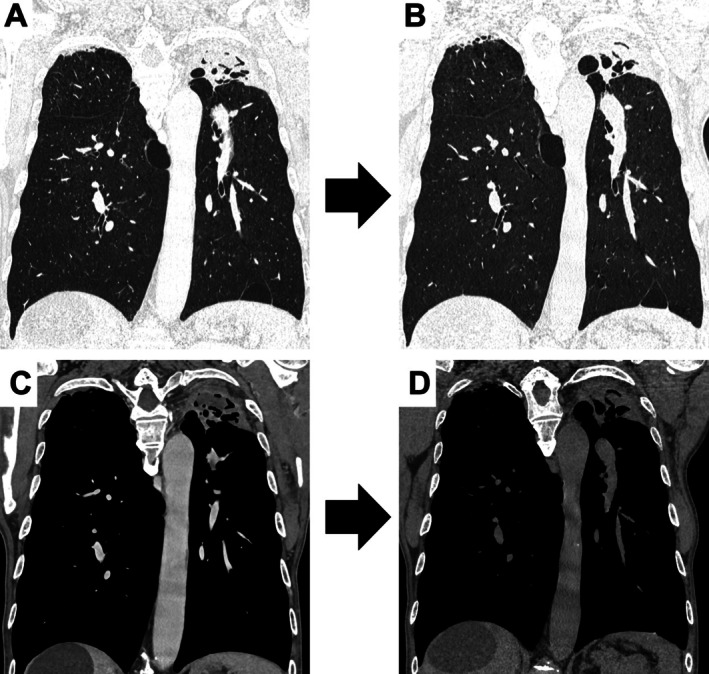

一位76岁的男性被诊断为左上肺叶曲菌瘤。由于高龄和结肠癌复发,手术不是一个选择。用活检钳切除曲菌瘤。然后,病变和痰液减少。可以考虑支气管镜切除,特别是对于没有手术指征的患者。

A 76-year-old man was diagnosed with aspergilloma in the left upper lobe. Due to advanced age and recurring colon cancer, surgery was not an option. The aspergilloma was removed with biopsy forceps. Then, the lesion and sputum were decreased. Bronchoscopic removal can be considered, particularly for patients without surgical indications.